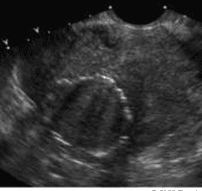

U xơ cơ tử cung dưới niêm mạc lâm sàng thường gây rong kinh, rong huyết